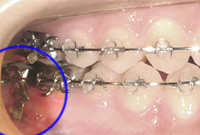

歯科矯正用アンカースクリュー

そこで、「完全な固定源」を求めて歯科矯正用アンカースクリューや歯科矯正用アンカープレートを固定源とした矯正治療が開発されました。これは、上顎の唇頬側歯槽部や口蓋に小さな器具を埋入留置することより、固定源を確保して治療を行うものです。

歯科矯正用アンカースクリューの特徴

手術侵襲がほとんどなく、短時間で術後の腫れもほとんどない治療方法ですが、一部の患者様で治療中にこれらの歯科矯正用アンカースクリューが脱離することがあります。